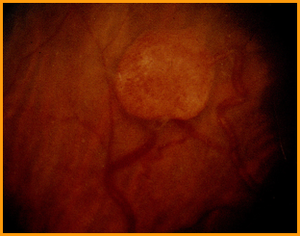

Von HIppel-Lindau Syndrome:

Autosomal dominant disorder (VHL gene on Chrom 3= tumor suppressor gene- may play role in exit from cell cycle)

Prevalence of approximately 1:40.OOO.

Tumors include:

- “retinal angioma” (hemangioblastoma),

- hemangioblastomas of brain and spinal cord

- renal cell carcinoma

- pheochromocytomas.

Below: renal cell carcinoma